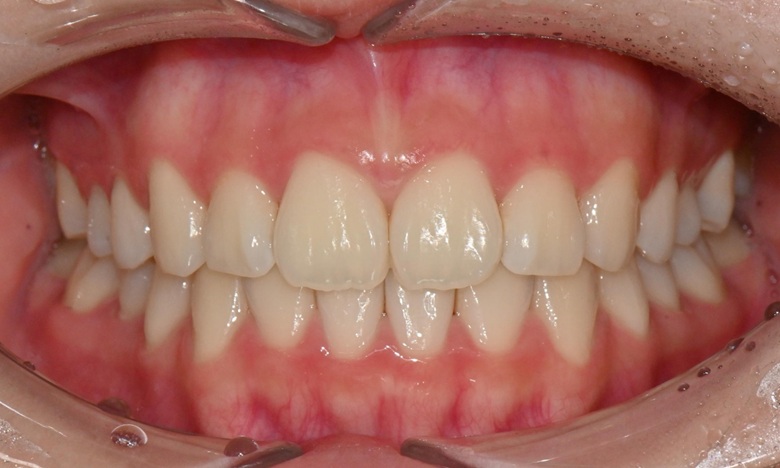

치료 후 전치부 배열이 정리되면서 웃을 때 스마일 라인도 한층 자연스럽게 개선되었습니다. 과개교합 역시 기능적으로 안정된 상태로 마무리할 수 있었습니다. 치료 후반부에 아주 경미한 중심선 차이가 남아 추가 장치를 통한 마무리를 권유드렸으나, 환자가 고2 학생으로 학업 일정이 바쁜 시기였고 현재 결과에 대해 본인과 보호자 모두 충분히 만족하여 이 상태에서 치료를 종료하기로 하였습니다.

치료 전후 스마일 라인 - 연세정원치과

무엇보다 이 환자는 8개월 동안의 치료 전반에 걸쳐 장치 착용을 매우 잘 지켜준 성실한 학생이었고, 그 결과 비교적 33단계의 효율적인 장치 갯수만으로도 안정적이고 만족스러운 결과를 얻을 수 있었습니다.